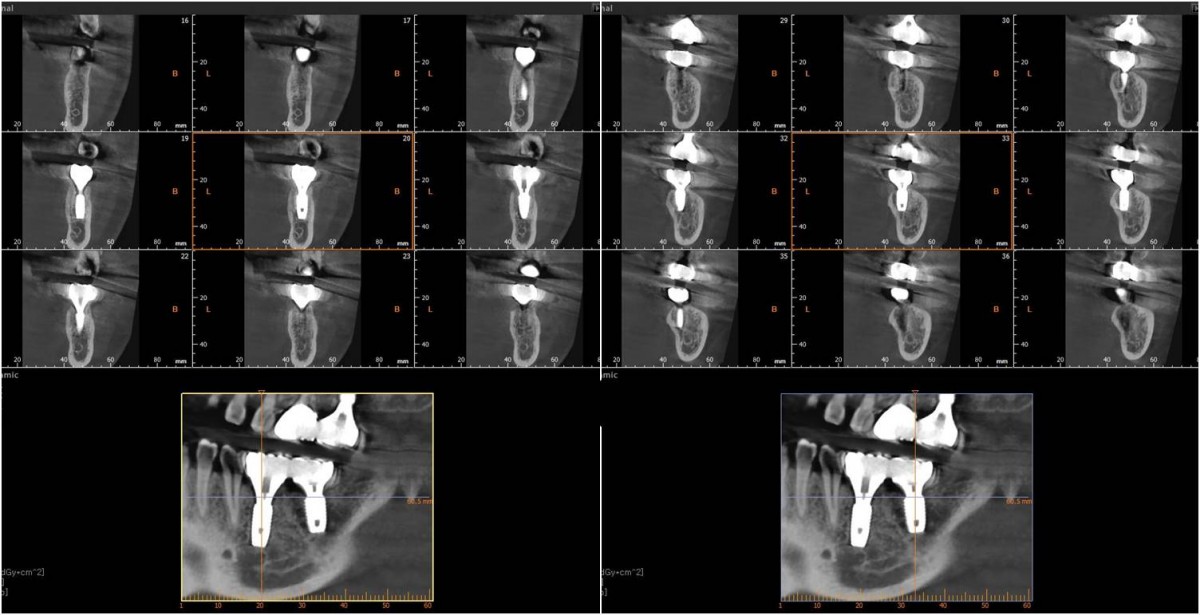

▲Panoramic radiograph before the implant surgery in the lower left area.